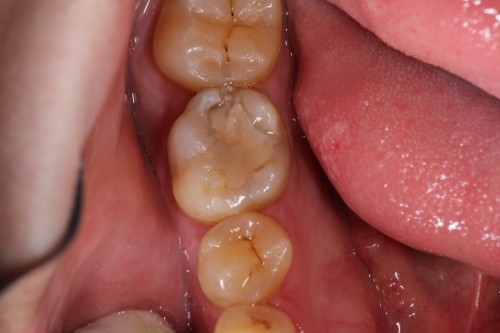

奥歯がしみるとの事でした。一見分かりませんが拡大鏡で確認して行くと虫歯が見つかりました。

虫歯を取った状態です。虫歯のみを取っています。

ここにマトリックスという金属製の薄い器具を入れて行き歯の形をなるべく再現できる様にします。

治療後の状態です。通常の型とりをする治療だと今回の数倍歯を削る事になります。歯は削れば削る程、脆くなりますので治療する事で歯の寿命を縮める事にもなり兼ねません。今回、最小限度のダメージで回復できました。歯も長持ちする事でしょう。

ダイレクトボンディング

費用6万円

リスクとして欠ける可能性がある(修復可能)。